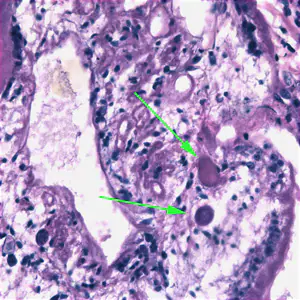

Migrating spargana cause various symptoms depending on the final location in the host. Spargana may locate anywhere, including subcutaneous tissue, breast, orbit, urinary tract, pleural cavity, lungs, abdominal viscera and the central nervous system. The migration in subcutaneous tissues is usually painless, but when spargana settle in the brain or spine a variety of neurological symptoms may occur, including weakness, headache, seizure, and abnormal skin sensations, such as numbness or tingling. If the inner ear is involved, the patient may experience vertigo or deafness. Occasionally, Sparganum proliferum can cause proliferative lesions in the infected tissue, with multiple plerocercoids present in a single site.

Proliferating spargana in groin tissue.